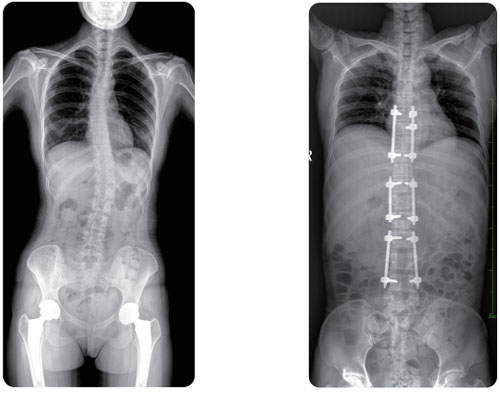

Full spine in one image No additional stitching required

The idea of full spine in one exposure has a significant value in the clinical usage of lumbar degenerative diseases, ankylosing spondylitis, spinal tuberculosis etc.

Giving a thorough examination of fracture site under the fluoroscopy image, as well as performing preoperative and postoperative diagnosis. E.g. oblique position of spine, pars interarticularis etc.

Observing the whole spinal motion through fluoroscopy, as well as mobility and bone structure of pathological spine. Guided by fast DSI to capture keyframes, enabling radiologist to deploy precise surgical plans.

Dynamic fluoroscopy also could be used in myelography, which serve as an radiologic diagnosis for multiple diseases like space occupying lesion of spinal canal, disc protrusion, spinal stenosis, spinal cord malformation and degenerative diseases etc.

Visualizing intramedullary nail

Intramedullary nailing is the most common minimally invasive surgery in orthopedics.

PLX8600 could be able to provide large filed of view for better demonstrating fracture site and nail position, e.g. those IM nails implanted in femur and humerus in particular.

One photograph for both lower limbs, no additional stitching required. Measuring funciton is also available, which is easy for radiologist to record the data for accurate diagnosis.